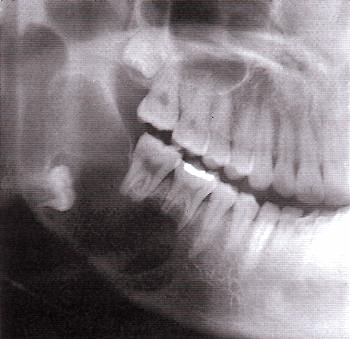

Рентгенологическая картина

Возможны следующие варианты амелобластомы:

1. Ряд округлых полостей.

2. Одна костная полость, окруженная множеством более мелких полостей.

3. Ряд округлых полостей, в 1-2 из которых заключен зубной фолликул или сформированный зуб.

4. Многоугольные полости.

5. Крупнопетлистая структура кости за счет множества мелких кист.

6. Несколько единичных крупных кистозных полостей.

7. Одна большая кистозная полость с неровными краями.

8. Одна большая полость, в которую обращены корни зубов (напоминает радикулярную кисту).

9. Одна большая киста, в которую обращена коронковая часть непрорезавшегося зуба. Этот вариант напоминает фолликулярную кисту.

Важнейшей рентгенологической чертой адамантином является различная степень прозрачности тени полостей особенно четко выраженной в поликистозных адамантиномах. Центральные отделы кистозных полостей прозрачнее, чем краевые. В однокамерных адамантиномах удается видеть полоску полутени вдоль костных границ опухоли. Нередко отмечается резорбция корней зубов в области опухоли.